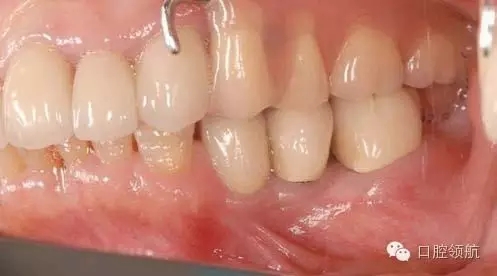

圖9 重新植入種植體5年后的口內(nèi)像。